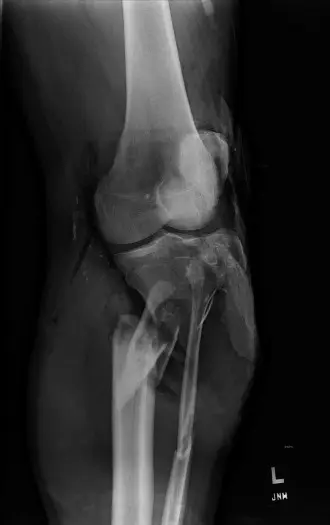

## أنواع كسور الساق المفتوحة وتصنيفها

تُصنف كسور الساق المفتوحة بناءً على شدة الجرح ودرجة التلوث وتلف الأنسجة الرخوة، وهو تصنيف حيوي لتحديد خطة العلاج والتنبؤ بالنتائج. يعتبر نظام Gustilo-Anderson الأكثر شيوعًا:

* **النوع الثالث (Type III):** وهو الأكثر خطورة وتعقيداً، ويقسم إلى:

* **III C:** كسور مفتوحة من النوع III A أو III B، ولكن مع إصابة شريانية تتطلب إصلاحاً جراحياً، بغض النظر عن درجة تلف الأنسجة الرخوة. هذا هو النوع الذي نركز عليه بشكل خاص في هذا الدليل، وهو يتطلب أعلى مستويات الخبرة الجراحية، والتي يتميز بها الأستاذ الدكتور محمد هطيف.

2. **التصوير الطبي:**

* **الأشعة السينية (X-rays):** صور متعددة للكسر من زوايا مختلفة لتقييم نمط الكسر، درجة التفتت، وجود أجسام غريبة معدنية.

* **الأشعة المقطعية (CT Scan):** توفر صوراً ثلاثية الأبعاد أكثر تفصيلاً للعظم وتساعد في التخطيط الجراحي، خاصة في الكسور المعقدة والمفصلية.

* **تصوير الأوعية الدموية (Angiography) أو الأشعة المقطعية الوعائية (CT Angiography):** ضرورية لتحديد موقع ومدى إصابة الشرايين. يمكن أن تكشف عن تمزقات، انسدادات، أو تشنجات وعائية.